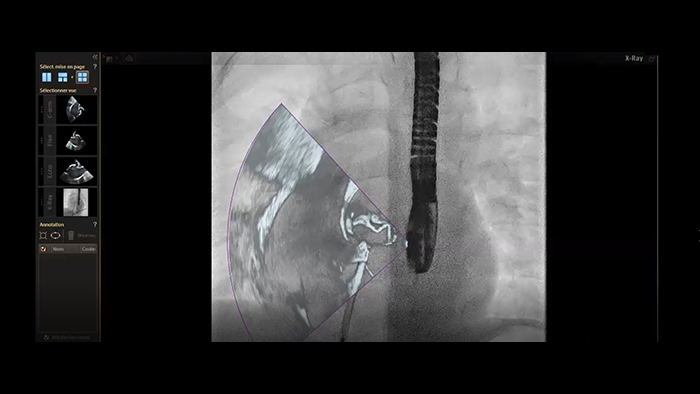

Cierre de la comunicación interauricular con fusión en tiempo real de EchoNavigator